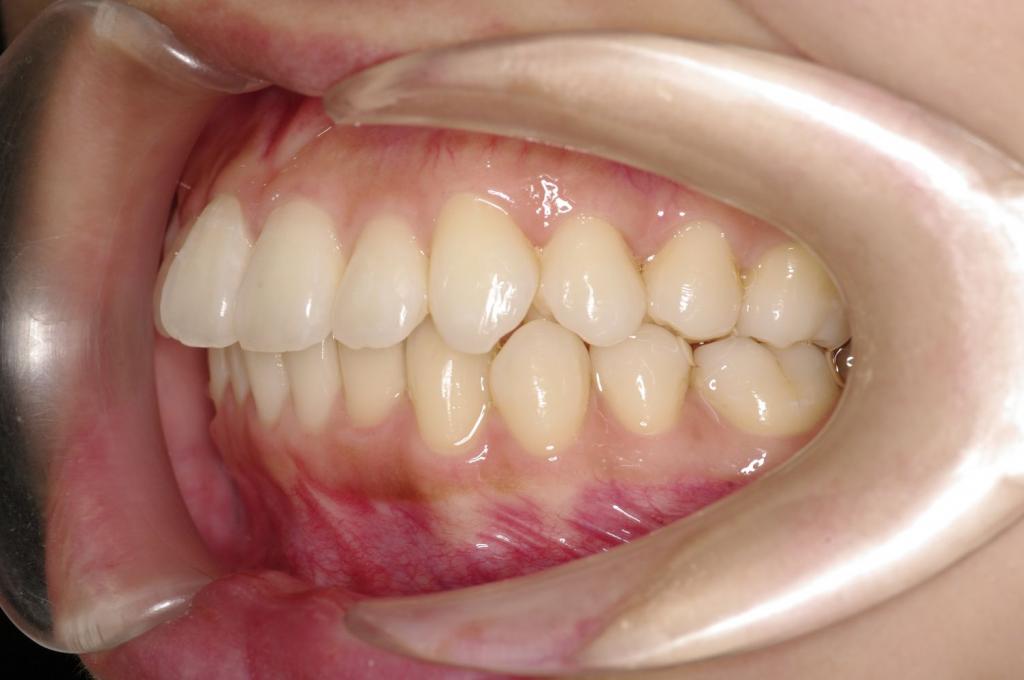

前歯、出っ歯・開咬の矯正治療